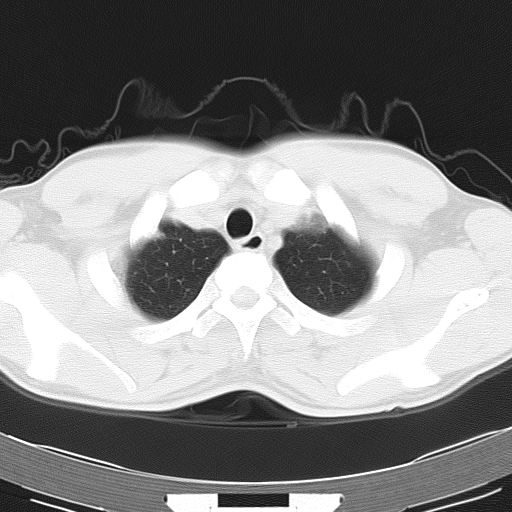

两上肺磨玻璃样改变,均位于肺外周,考虑1、肺泡蛋白沉着症?2、肺泡炎?请询问有无养鸟史 3、脱屑性间质性肺炎?建议进一步检查、复查随访

两上肺的ggo,靠近胸膜,不是以节段分布,青年男性,个人意见为吸入性的真菌感染可能为大------------呼吸内科医生

两肺上叶近胸膜磨玻璃样阴影,考虑1、炎性病变。 。2、过敏性炎症?

病灶特点:

分布在肺野的外带,病灶边缘清楚,病灶以磨玻璃影为主夹杂少许纤维状高密度影

支持zhangzhongshou主任,考虑蛋白沉着症可能性大

(1)斑片状磨玻璃影:指肺野密度朦胧增加,内可见肺血管纹理影,系肺泡腔内充满低密度的磷脂蛋白物质所致。

(2)其内部小叶间隔或小叶内间隔增厚所形成的网格状影,为小叶间隔水肿、肺泡壁内淋巴细胞和巨噬细胞浸润以及小叶内淋巴管扩张的缘故。

(3)病灶边缘清楚,呈地图样分布于肺野外围或肺门及中央区。

病变分布以双上肺叶外带明显,双下肺未见异常,此一点不十分支持肺泡蛋白质沉着症,病变未见铺碎路石征,也不肺泡蛋白质沉着症。考虑间质性肺炎,结核不除外。

肺泡蛋白沉积症;胸膜下区磨玻璃样,实变区见纹理走形,地图样改变。做mri。

ct表现 (1)中央型:表现为蝶翼状浸润性阴影对称分布于两侧肺门周围,其内可见支气管充气征,病变区与正常肺组织分界清楚。(2)外围型:表现为多发性条片状、斑片状及斑块状高密度影,弥散、对称或不对称分布于两肺或一侧肺外围部位。病变区与正常肺组织及脏层胸膜面分界清晰,呈地图样改变。hrct可显示小叶间隔增厚及肺小叶内淡淡的密度增高影等细微结构,同时易发现肺大疱、肺气囊及节段性肺不张。

再仔细阅读该病人的ct片,我们不难发现,病例所表现的正是外围型的肺泡蛋白沉积症表现,即:为多发性条片状、斑片状及斑块状高密度影,弥散、对称或不对称分布于两肺或一侧肺外围部位。病变区与正常肺组织及脏层胸膜面分界清晰,呈地图样改变。